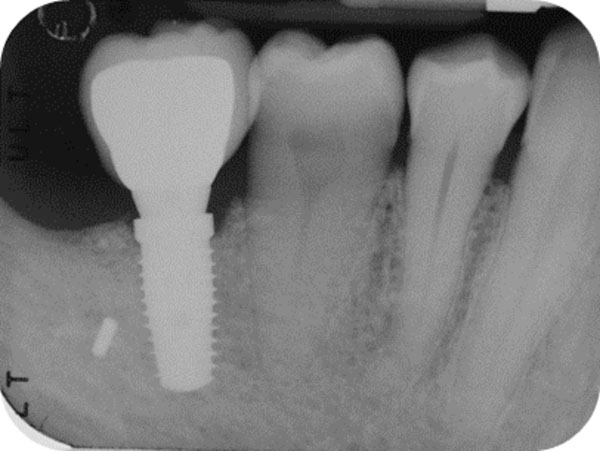

Follow-up x-ray at 24 months displaying the stable maintenance of the peri-implant bone tissue levels and no sign of bone resorption.

After 15 days, the soft-tissue healing was uneventful, and the previously established prosthetic protocol was followed. A single-crown definitive restoration was delivered 1 month (Fig. 11a, 11b). The prosthesis was placed in occlusion, where the occlusal surface was thoroughly modeled, so that it was in contact with reduced areas during laterality and protrusion excursions, in order to reduce the dislocating vectorial components; more contacts were maintained in maximum intercuspation. Follow-up radiographs were taken at 1, 12, and 24 months after prosthesis delivery (Fig. 12, 13, 14).

One year after surgery, clinical examination showed no significant changes in the soft-tissue contours. All follow-up radiographs taken up to 24 months after implant placement showed complete maintenance of the peri-implant bone levels without any sign of bone resorption. The grafted site was perfectly able to support the functional loading of the implant.

The histologic results appear to correlate with the good clinical outcome documented by the intraoral x-rays. Indeed all follow-up controls showed complete maintenance of the peri-implant bone levels without any sign of bone resorption. The healed bone was perfectly stable up to 24 months after bone augmentation, supporting the functional loading of the implant. A possible explanation of the maintenance of bone levels and stability over time is the nearly complete resorption and substitution of the heterologous biomaterial by newly formed functional bone tissue together with the restoration of the masticatory load. The fact that control x-rays maintained the same appearance over time, showing the first implant threads in strict contact with a bone-like area, as far as both structure and radio-opacity are concerned, also suggests that the heterologous bone material may have undergone a remodeling process leading to the osseointegration of the fixture also in the biomaterial-only grafted region.